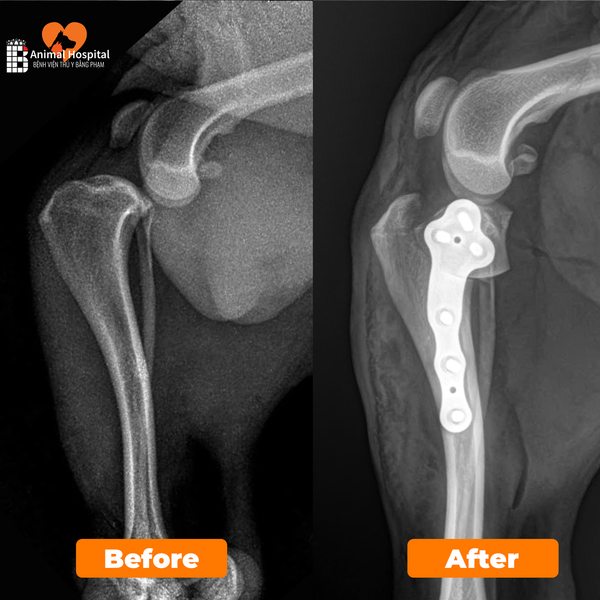

Dịch Vụ Phẫu Thuật Chỉnh Hình Xương Khớp

Thực hiện điều trị gãy xương, trật khớp và dị tật vận động bằng các kỹ thuật cố định tiên tiến như nẹp vít titan, giúp phục hồi chức năng vận động an toàn và bền vững cho thú cưng.